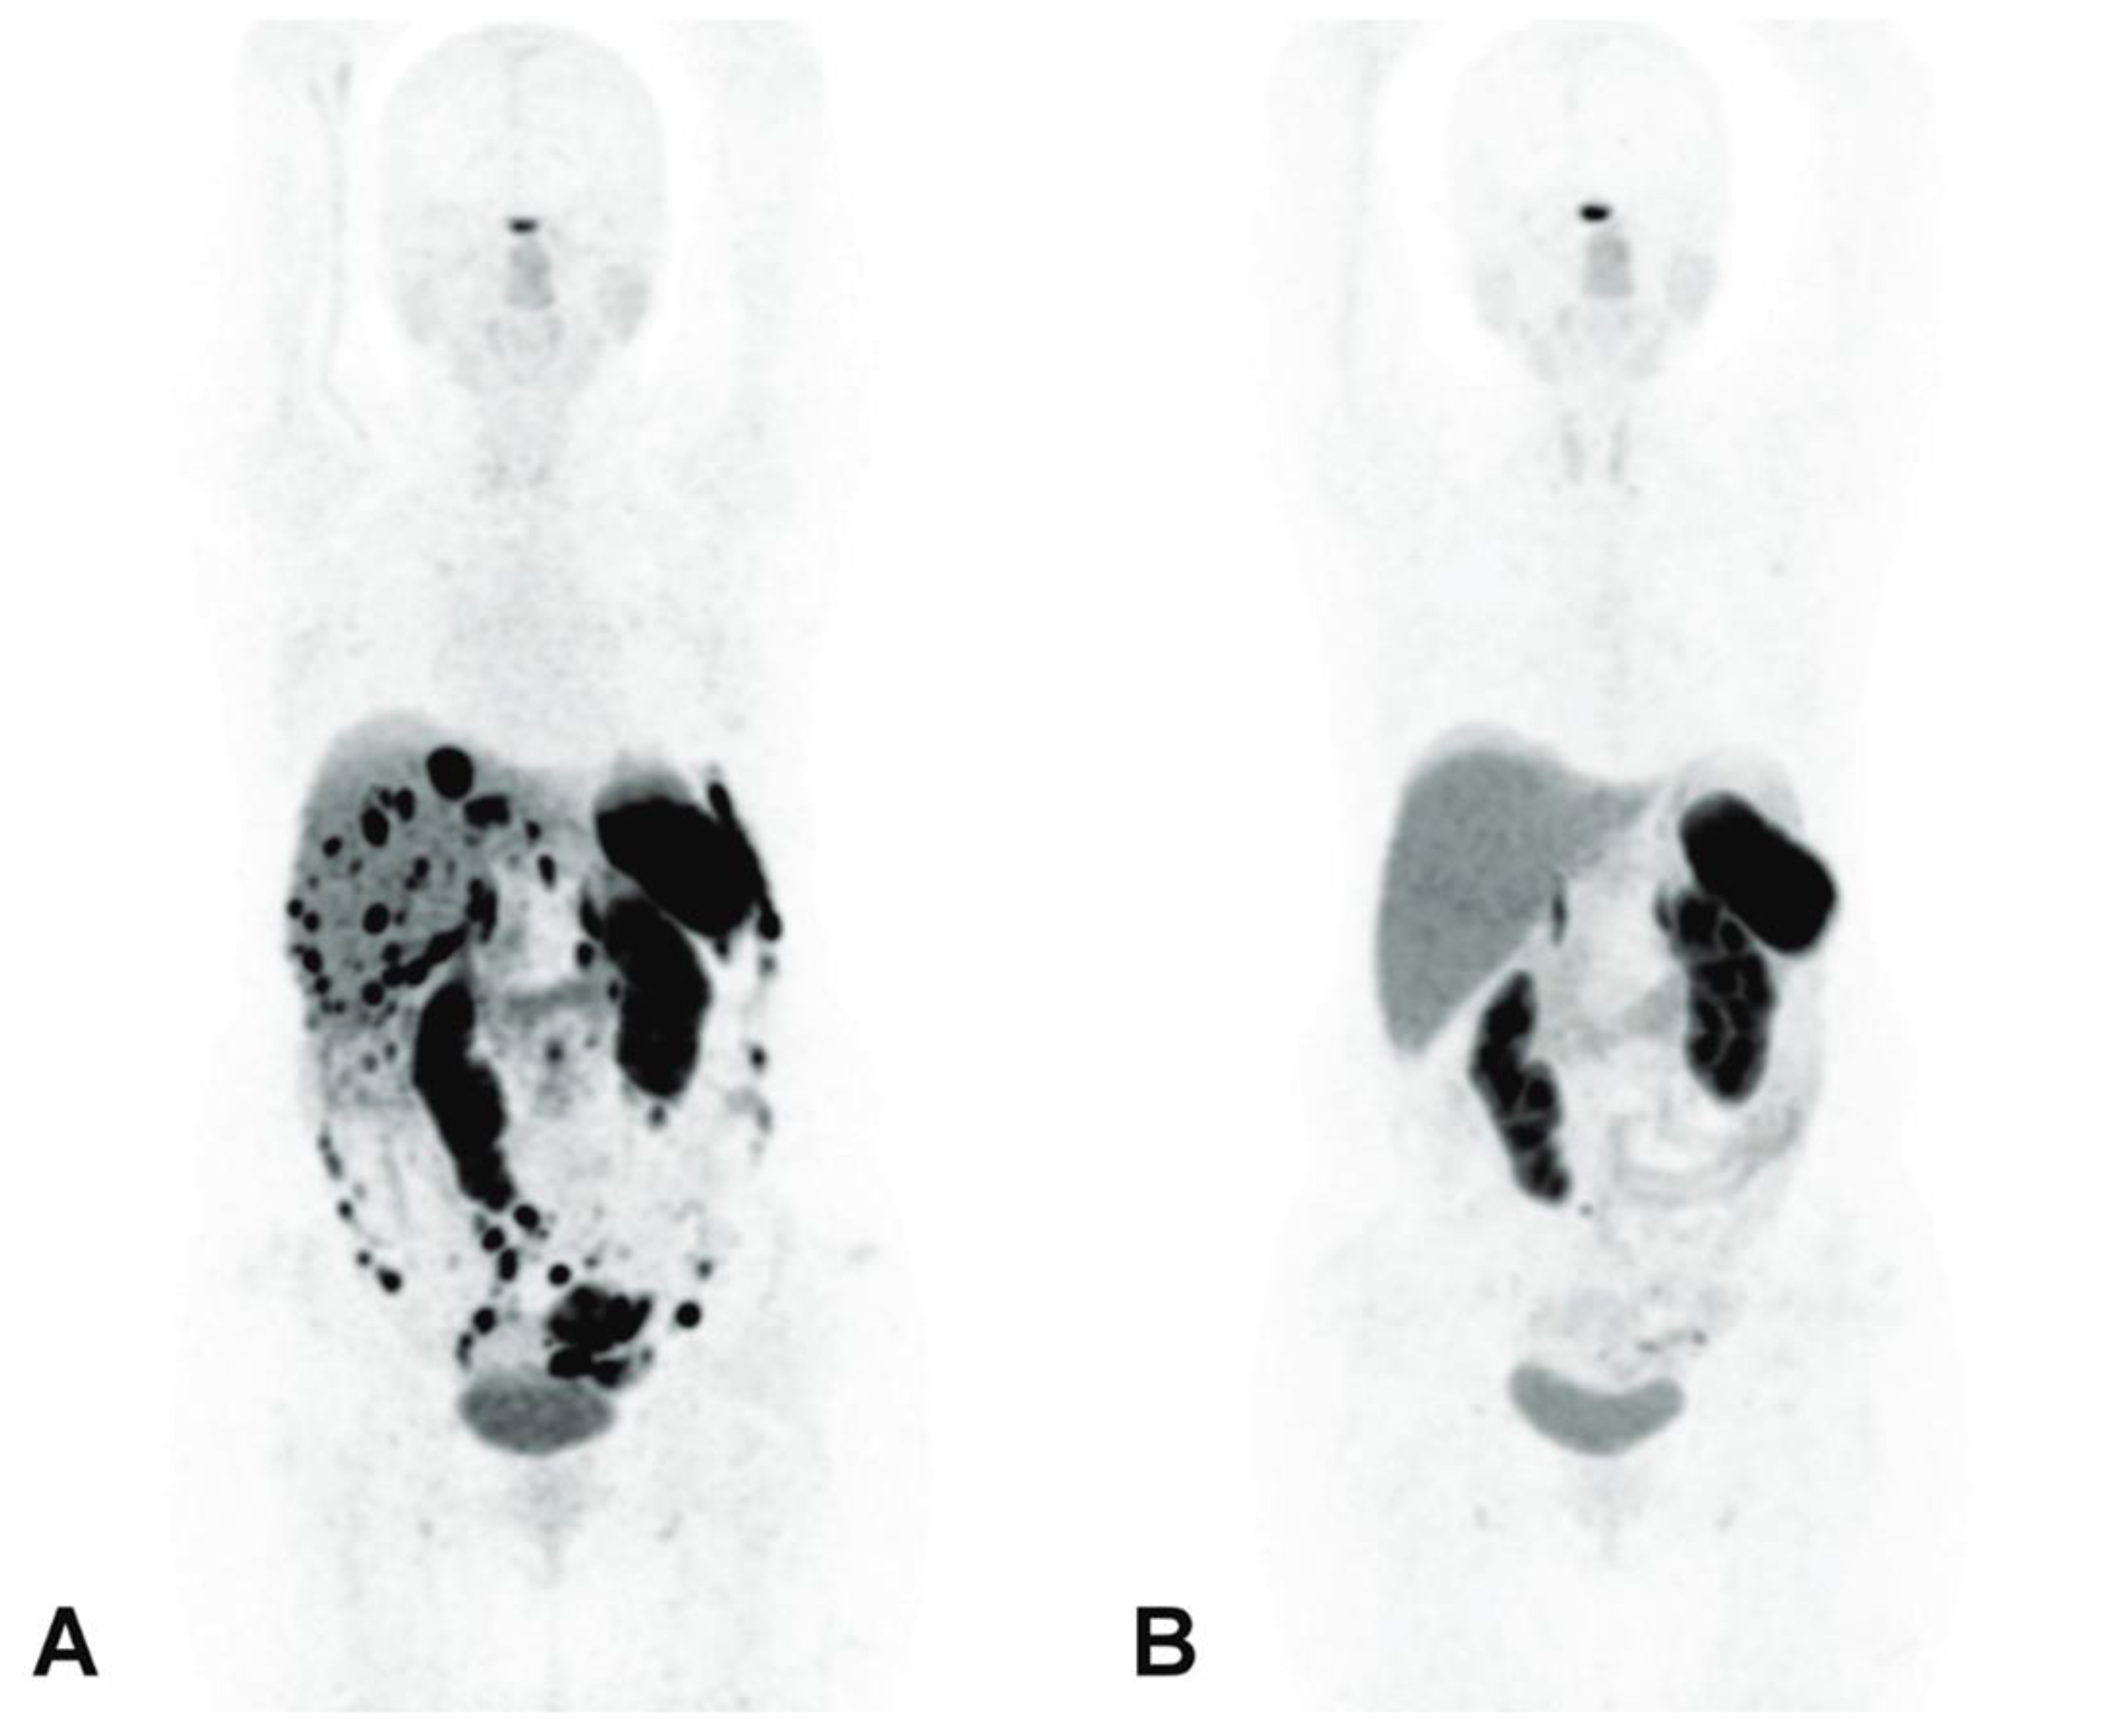

- Zhang, J.; Kulkarni, H.R.; Baum, R.P. Peptide Receptor Radionuclide Therapy Using 225Ac-DOTATOC Achieves Partial Remission in a Patient with Progressive Neuroendocrine Liver Metastases after Repeated β-Emitter Peptide Receptor Radionuclide Therapy. Clin. Nucl. Med. 2020, 45, 241–243. [Google Scholar] [CrossRef]

- Alan Selçuk, N.; Demirci, E.; Ocak, M.; Toklu, T.; Ergen, S.; Kabasakal, L. Almost Complete Response with a Single Administration 225Ac-DOTATATE in a Patient with a Metastatic Neuroendocrine Tumor of Unknown Primary. Mirt 2022, 31, 139–141. [Google Scholar] [CrossRef]

- Satapathy, S.; Sood, A.; Das, C.K.; Kavanal, A.J.; Mittal, B.R. Alpha Before Beta: Exceptional Response to First-Line 225Ac-DOTATATE in a Patient of Metastatic Neuroendocrine Tumor with Extensive Skeletal Involvement. Clin. Nucl. Med. 2022, 47, e156–e157. [Google Scholar] [CrossRef] [PubMed]

- Budlewski, T.; Król, Z.J.; Bruchertseifer, F.; Majkowska-Pilip, A.; Morgenstern, A.; Wierzba, W. Innovative Radioisotope Therapy for Patients with Neuroendocrine Tumors Using an Alpha (225Ac) Emitter Labeled Somatostatin Analog: Octreotate. A Promising New Treatment for Advanced, Progressive Neuroendocrine Neoplasms. Pol. Arch. Intern. Med. 2022, 132, 16275. [Google Scholar] [CrossRef] [PubMed]